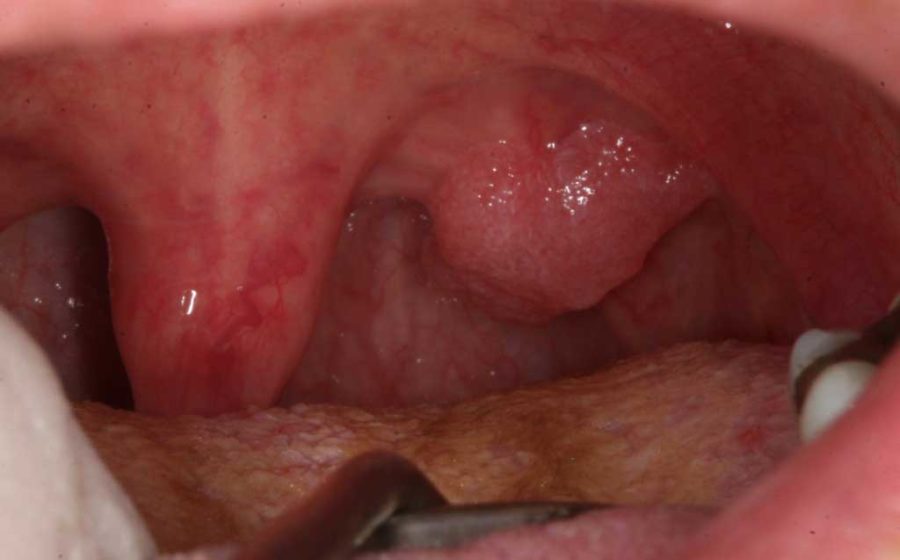

Метод радиоволновой эксцизии шейки матки

1. Доктор удаляет образование на шейке матки петлевым электродом либо за один проход, либо чаще – за несколько проходов. См на фото.

2. Доктор шариковым электродом обрабатывает рану, проводит радиоволновую коагуляцию кровоточащих сосудов и выравнивает рану на шейке матки. См на фото.